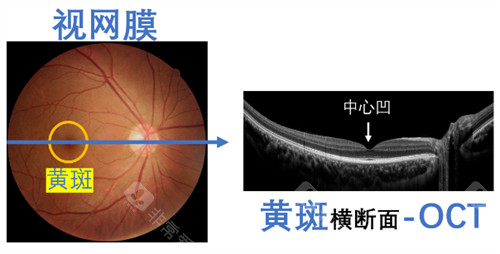

实例一:65岁男性患者,因"右眼视力突然下降伴视物变形"就诊。经检查确诊为右眼黄斑裂孔,视力仅0.1。雷医生为其进行了小创口玻璃体切割联合内界膜剥除手术,术后3个月复查,黄斑裂孔闭合,视力修复至0.6。

医院眼底病专科设备可靠,拥有国内外很棒的眼科检查及手术设备,包括光学相干断层扫描仪(OCT)、眼底荧光造影仪、视觉电生理检查仪、超声生物显微镜(UBM)等。

中心开展各种黄斑疾病的诊断和治疗,包括老年性黄斑变性、黄斑水肿、黄斑裂孔、黄斑前膜等,年手术量超过1000例。